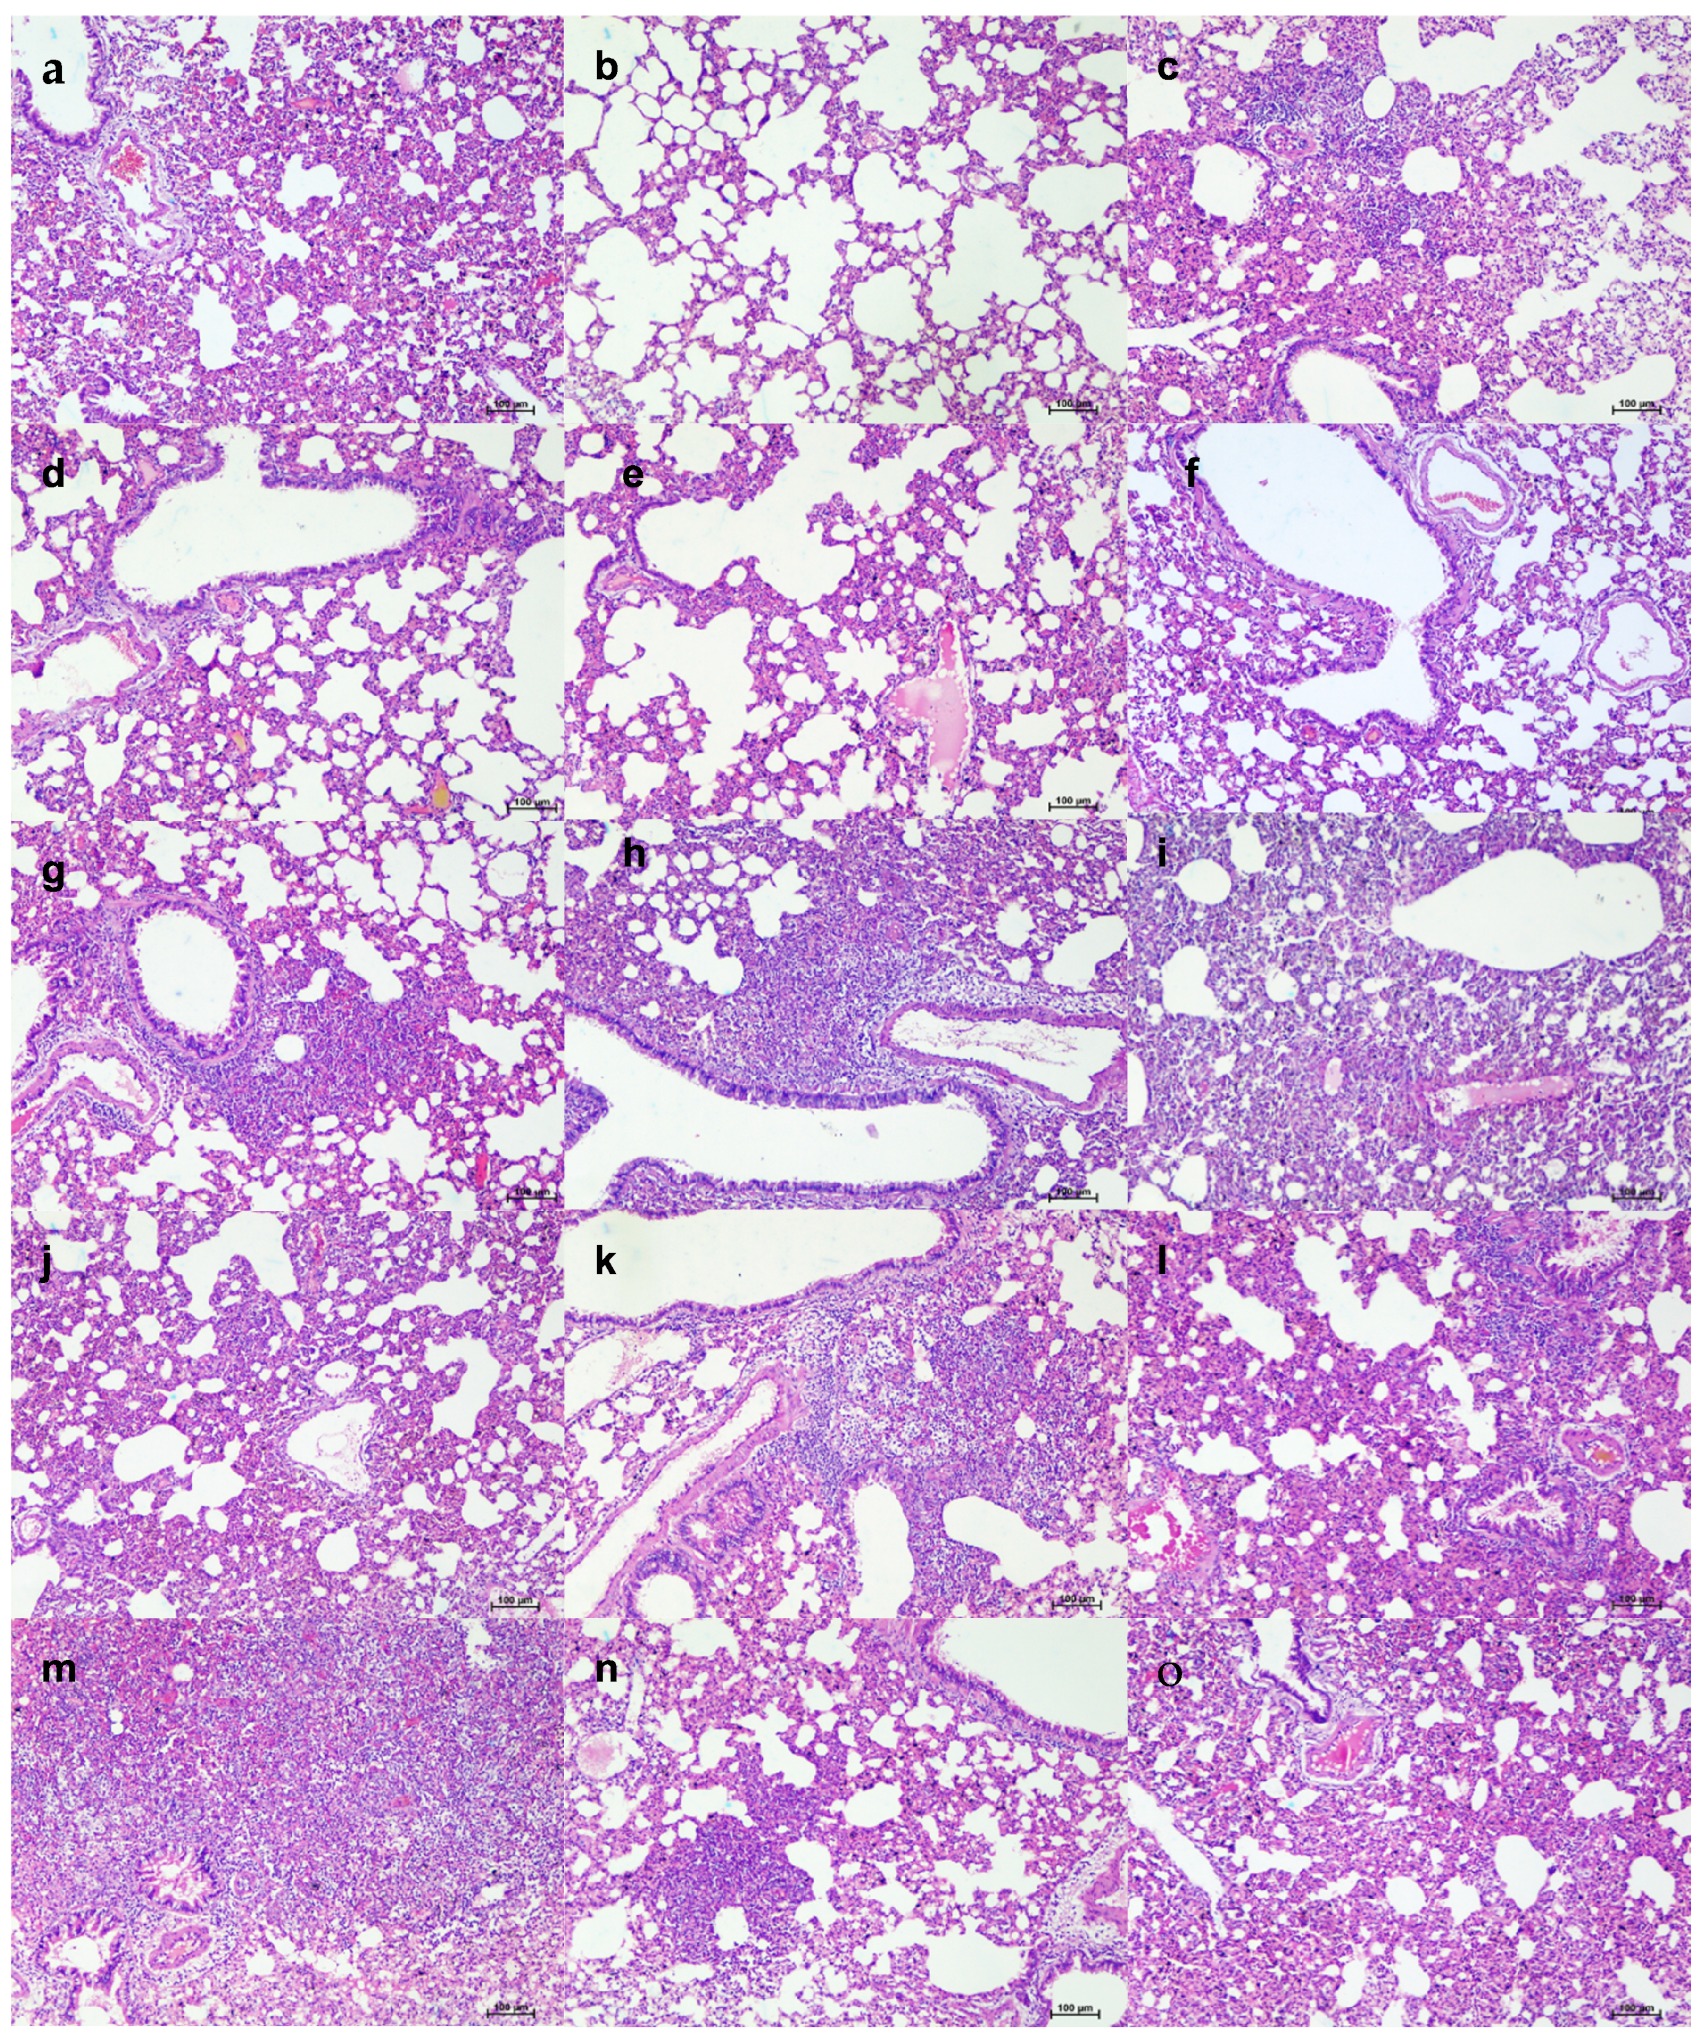

Grossly, mild congestive changes were observed in lungs in all the mAb-treated and control groups on 3 DPI. On the fifth DPI, congestion and hemorrhagic changes were more prominent in the 1 mg/kg dose group, isotype antibody, and placebo groups. Lungs of the 50 and 5 mg/kg groups appeared normal or with minimal gross changes on 5 and 7 DPI. The proportion of lungs’ weight to body weight in hamsters was also significantly higher in the placebo group (p < 0.05) on 5 DPI compared to the mAb administered group (Figure 4h). On histopathological examination, the 50 mg/kg and 5 mg/kg dose groups showed mild changes on 3, 5, and 7 DPI (mild alveolar consolidation, focal septal thickening, and inflammatory cell infiltration), whereas the 1 mg/kg group and placebo group showed moderate lesions (diffuse exudative changes in the alveolar lumen, septal thickening, and marked inflammatory cell infiltration in the interstitial space and in the peri bronchial region). The isotype antibody control showed severe pneumonic changes of diffuse involvement compared to other groups (Figure 4e and Figure 5).

Figure 5.

Histopathological observations in lungs of hamsters treated with ZRC3308 cocktail prophylactically. Lungs of the placebo group (a) on 3DPI showing congestion and focal area of consolidation, scale bar = 200 µm (b) on 5 DPI showing diffuse areas of consolidation, congestion, and mononuclear infiltration, scale bar = 100 µm (c) on 7 DPI showing congestion and consolidation, scale bar = 200 µm. Lungs of 50 mg/kg dose prophylactic group (d) on 3DPI showing alveolar capillary congestion, scale bar = 100 µm (e) on 5DPI and (f) 7DPI showing alveolar septal thickening and congestive changes, scale bar = 100 µm. Lungs of 5 mg/kg dose group on (g) 3 DPI, scale bar = 200 µm (h) 5 DPI and (i) 7 DPI showing congestive changes, scale bar = 200 µm. Lungs of 1 mg/kg dose group on (j) on 3DPI showing congested vessels, (k) on 5DPI and (l) 7DPI showing congestion and foci of mononuclear cell infiltration in the peri bronchial region, scale bar = 200 µm. Lungs of the isotype antibody control group on (m) 3 DPI showing severe congestion, scale bar = 200 µm (n) on 5DPI showing diffuse pneumonic changes, scale bar = 200 µm and (o) on 7 DPI showing alveolar septal thickening and consolidation, scale bar = 200 µm.